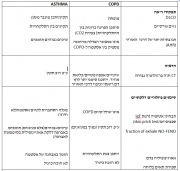

| 21:29, 5 במרץ 2015 | AsthmaCOPD3.jpg (קובץ) |  |

380 קילו־בייטים | Motyk | 1 | |